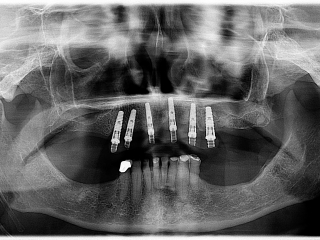

This is a wonderful case of a patient who had failing bridges for years. The upper teeth had been failing and the patient had experienced moderate bone resorption (bone shrinkage due to early loss of teeth).Due to the advancement of implant surgery the patient was able to have a full set of teeth supported by 6 implants. The maxilla (upper arch) had 6 implants placed into the alveolar bone and a temporary set of teeth were immediately screwed into the implants. The implants in combination with the teeth heal for a minimum of 9 months then a new set of teeth are placed onto the implants. The new teeth are supported by a titanium bar and wrapped around the bar is acrylic (gums) and teeth.